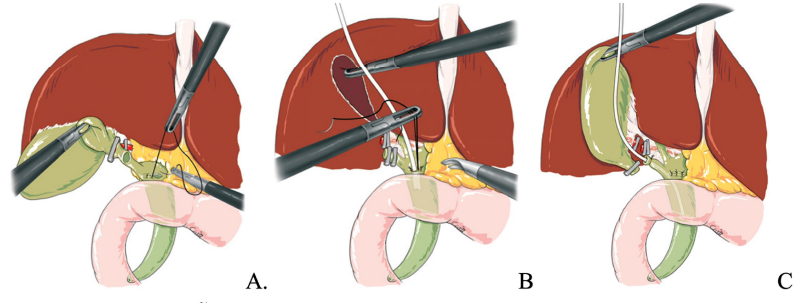

Kéo lấy sỏi:

- Qua ngả ống túi mật: Giải phẫu ống TM thuận lợi, sỏi nhỏ, số lượng ít và được kiểm soát kỹ.

- Qua mở OMC:

- Với những sỏi nhỏ (<10mm): có thể kéo lấy qua ngả ống túi mật;

- với sỏi lớn hơn cần mở OMC để lấy sỏi.

Hình. Lấy sỏi qua ngả ống túi mật.

A. Kéo lấy sỏi với Dormia dưới hướng dẫn màn tăng sáng.

B. Kéo lấy sỏi với Dormia dưới hướng dẫn ống nội soi mềm đường mật

Hình. Mở OMC lấy sỏi qua PT nội soi (A). B. Lấy sỏi bằng pince; C. Bơm nước áp lực cao; D. Dùng rọ Dormia